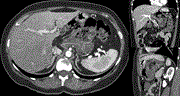

A huge hepatic angiomyolipoma with growth during 5 years of follow-up

Michio Machida and others

Journal of Surgical Case Reports, Volume 2020, Issue 9, September 2020, rjaa353, https://doi.org/10.1093/jscr/rjaa353